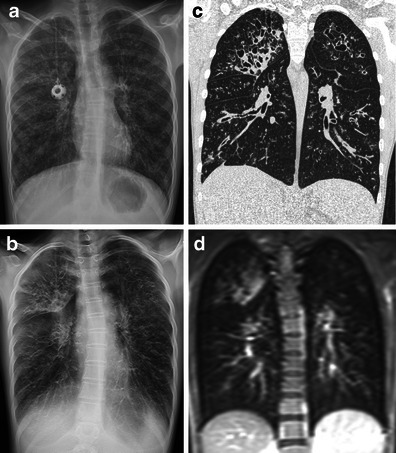

Morphology and immunohistochemistry of COPD-associated lung lesions. A: Chronic bronchitis. B: Centriacinar emphysema. C: Advanced active bronchitis with fibrosis and emphysema. A-C, hematoxylin-eosin staining; D: CD68-PPARG coexpression with double IHC staining using alkaline phosphatase [red cytoplasm-CD68] and diamino-benzidine [brown nuclei-PPARG]. E: Cells with red fluorescence and green nuclei DCSign-PPARG double fluorescence staining. Nuclear counter-staining is DAPI. Indications: b, bronchus; a, alveolar spaces; arrows, alveolar macrophages. Original magnifications: A-D 20×; E 40×. Analyses of association between PPAR gamma and EPHX1 polymorphisms and susceptibility to COPD in a Hungarian cohort, a case-control study. Penyige A, Poliska S, Csanky E, Scholtz B, Dezso B, Schmelczer I, Kilty I, Takacs L, Nagy L - BMC medical genetics (2010). Not Altered. CC.